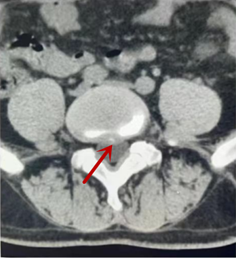

利器二:CT

CT利用X射線對(duì)人體檢查部位通過(guò)電腦切成若干層掃描,然后把每層的圖像都能顯示出來(lái)。CT相對(duì)于X光片具有更高的密度分辨力,可直接顯示X線片無(wú)法顯示的病變,觀察腰椎有無(wú)微小的骨折、骨質(zhì)有無(wú)破壞等骨質(zhì)情況、以及腰椎間盤(pán)突出、腰椎神經(jīng)根、椎管、椎間小關(guān)節(jié)的情況等。同時(shí)還可以通過(guò)后處理,重建腰椎矢狀位或冠狀位圖像,形成腰椎的3D圖像,更直觀地觀察病變部位,對(duì)腰椎手術(shù)風(fēng)險(xiǎn)具有提示作用,對(duì)手術(shù)方式的選擇具有指導(dǎo)意義,但是對(duì)神經(jīng)、脊髓損傷程度的顯示不如MRI,軟組織的分辨率仍有一定限制,對(duì)椎管內(nèi)病變顯示欠佳,且有一定的輻射。

箭頭提示椎間盤(pán)突出